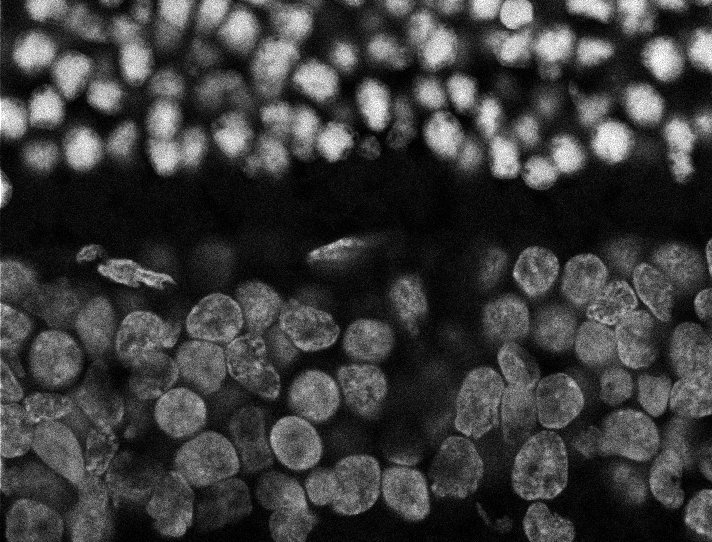

Nuclei

Nuclei - Bis

Nuclei - Bip

Nuclei - Bipolar